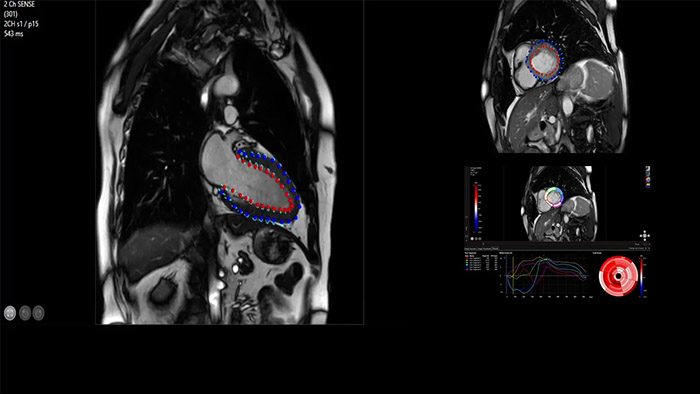

IntelliSpace Portal offers a Comprehensive Cardiac MRI Suite, providing dedicated workflows for functional analysis, viability, LGE, cardiac mapping assessment and RV/LV functional analysis in less than 5 min. per case1.

IntelliSpace Portal MR Caas5,6 Strain7 assists in patient diagnosis and monitoring by providing global strain parameters such as global longitudinal strain (GLS), global circumferential strain (GCS), and global radial strain (GRS), using short and long axis MR images, as well as describing the myocardium deformation- such as shortening, thickening, and lengthening during the cardiac cycle.